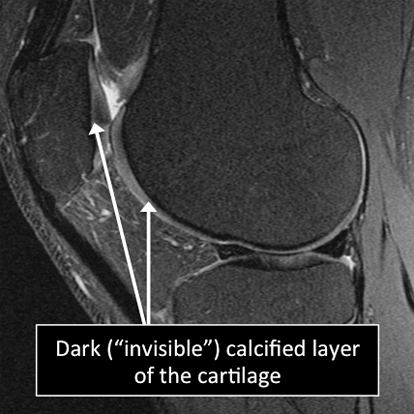

- In the cartilage, as in many other tissues of the body there are certain structures that can’t be seen (they look black or dark) with the standard MRI.

- There are new “software” programs that allow us to see structures with different contrast (bright versus dark).

- In the cartilage these “invisible” or dark structures include the calcified layer and the radial or deep zone of the cartilage.

Knee MRI examinations using the standarad MRI techniques (top) and translational MRI techniques (bottom).